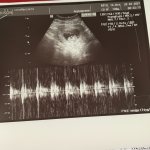

Расти наш малыш. Первый снимок 9 недель и 4 дня. Дата 29 марта 2021. На память . Думаю гематома рассосётся . Так как выделений нет и болей тоже нету ☺️у кого имплантация по передней стенке, расскажите в чем плюсы и минусы ☺️☺️☺️